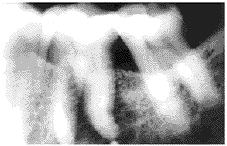

Figure 1a Case 3

Radiograph showing an ill-defined radiolucency associated with vital left lower first molar.

The interval between the diagnosis of the primary tumor and that of metastasis in the jaws varied. In our cases, it was from 3 months to 8 years. Bucin et al reported a case where metastasis developed 15 years after the breast carcinoma was first diagnosed[1]. Therefore, five year cure rate is not always significant and long term follow-up is necessary. Symptoms of metastasis when present are pain and swelling of the affected area. Pain may precede radiological evidence of the lesion by as long as 15 months[2] When the mandible is involved, the earliest sign may be anesthesia over the peripheral distribution of the inferior alveolar nerve on the affected side. Loosening of teeth without evidence of periodontitis or pathological fracture has also been stressed as a possible early sign. Pruckmayer et al demonstrated that toothache was the only sign in their four cases of metastatic breast caricinoma in the jaws[4]. In case 4 of our series, a 31 year-old female with a history of spontaneous pain in the area of the right upper central incisor, radiography showed an ill defined radiolucent area adjacent to the apex of the right upper central incisor (Fig 1a). A 1.5 cm slightly raised magenta-colored area on the facial gingiva over the root of the right upper central incisor was seen. The tooth was sensitive to cold. The clinical manifestaion of this case resembled a periapical inflammatory process except the tooth was sensitive to cold[11]. The patient had breast carcinoma which was treated surgically. She had just completed a course of chemotherapy. Her endodontist curetted the apical lesion. Histopathologic examination of the lesion showed an adenocarcinoma (Fig.1b). Chext x-ray revealed both lungs also had metastatic foci. She died 3 months after the metastatic lesions were discovered.